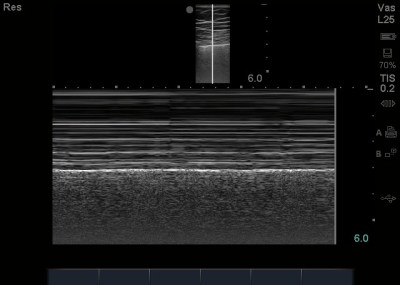

Since lung has air in it, and air is the enemy of US, deep to that sliding pleural line will have various other artifact that are not that diagnostic of anything (so dont pay too much attention to it). If you wanted to confirm that there is normal lung, without pneumothorax, you can use M-Mode or motion mode, which is essentially a waveform that detects motion. Once M-mode is pressed, you will find a line in the center of your screen – you want to place that line over the pleural line (avoid the rib). Once you press Mmode again, while keeping your probe very still (as it will detect that motion too), the top of the screen will be immobile (the muscles) and thus just straight lines going through, and the pleural line will be evident as a line, with the area posterior(deep) to that being grainy and without linear areas, denoting movement (in this case, of lung). Its called the sandy beach sign, or seashore sign (since to some, its looks like sand and water).